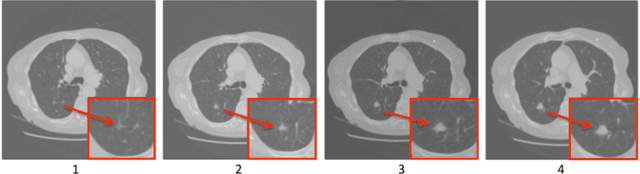

Abstract:Computed tomography (CT) generates a stack of cross-sectional images covering a region of the body. The visual assessment of these images for the identification of potential abnormalities is a challenging and time consuming task due to the large amount of information that needs to be processed. In this article we propose a deep artificial neural network architecture, ReCTnet, for the fully-automated detection of pulmonary nodules in CT scans. The architecture learns to distinguish nodules and normal structures at the pixel level and generates three-dimensional probability maps highlighting areas that are likely to harbour the objects of interest. Convolutional and recurrent layers are combined to learn expressive image representations exploiting the spatial dependencies across axial slices. We demonstrate that leveraging intra-slice dependencies substantially increases the sensitivity to detect pulmonary nodules without inflating the false positive rate. On the publicly available LIDC/IDRI dataset consisting of 1,018 annotated CT scans, ReCTnet reaches a detection sensitivity of 90.5% with an average of 4.5 false positives per scan. Comparisons with a competing multi-channel convolutional neural network for multi-slice segmentation and other published methodologies using the same dataset provide evidence that ReCTnet offers significant performance gains.